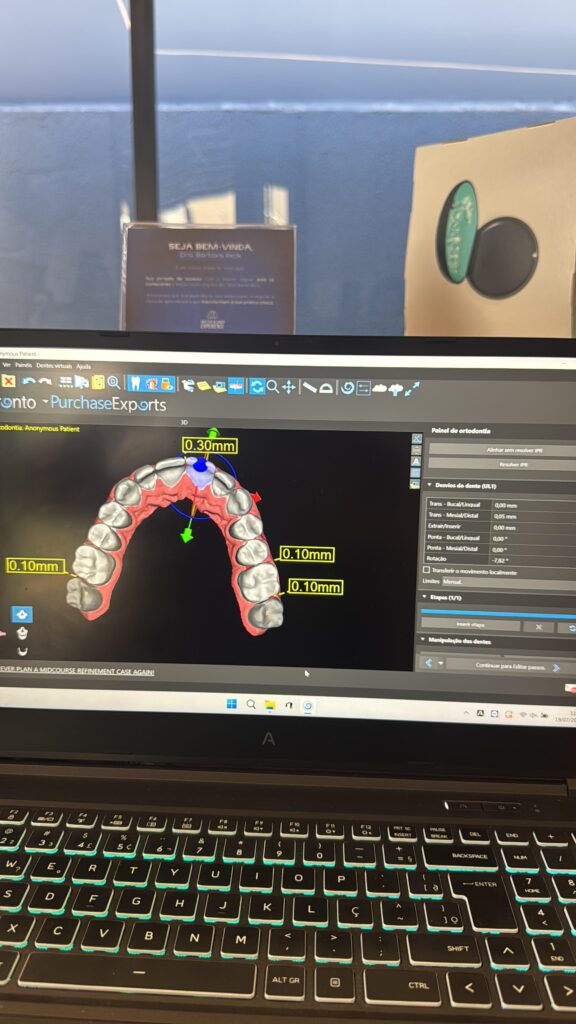

10:50 – Planejamento tridimensional: regiões seguras de inserção (maxila e mandíbula), planejamento digital e guias cirúrgicos

15:50 – Hands-on Parte 3: planejamento digital com guias cirúrgicos (Blue Sky Plan / STL)

Atua com alinhadores, planejamento digital e é referência regional na formação prática de dentistas.